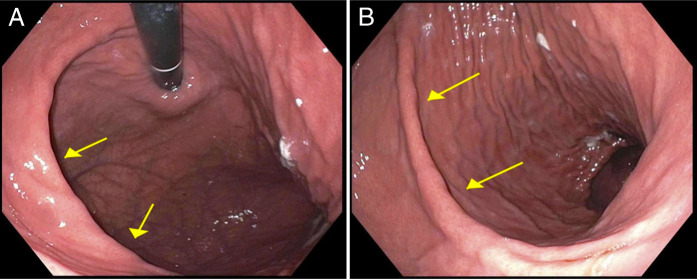

An Example of Cascade Stomach.